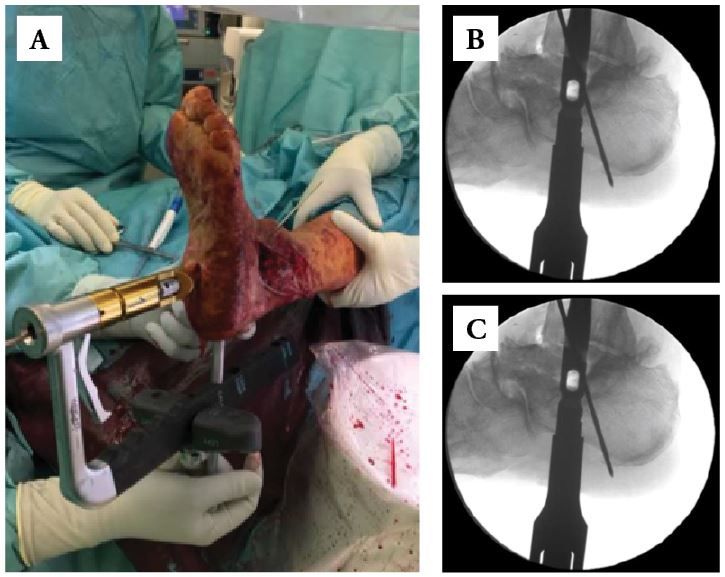

• Ream over the guidewire up to one millimeter greater than the proper nail size (Figs. 8-A and 8-B).

• Assemble the nail and test screw aiming guide precision.

• Insert the nail gently in a retrograde manner over the guidewire until fully seated in (Figs. 9-A, 9-B and 9-C).